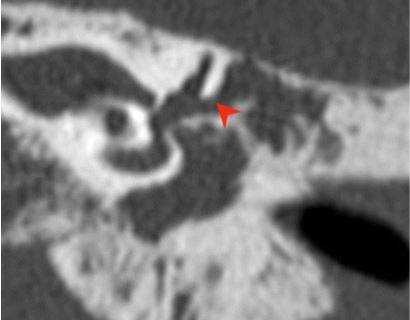

Хроническое воспаление среднего уха с холестеатомой: коронарная КТ показывает боковой свищ полукруглого канала (стрелка), вызванный эрозией кости из-за роста новообразования